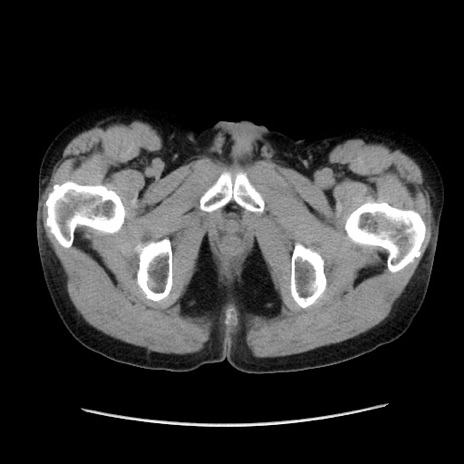

冠状断像